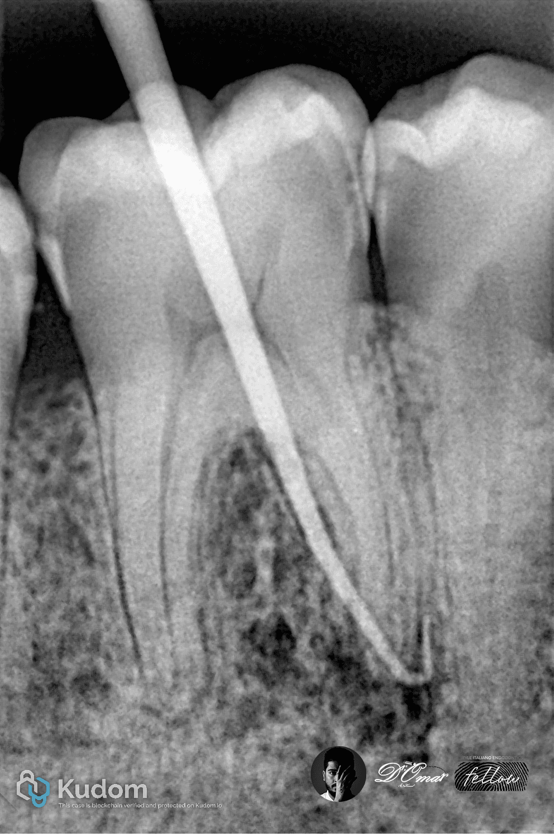

Fig. 4

Case No.2

Six-Canal Mandibular

Molar with Apical Lesion

A 41-year-old patient presented with spontaneous pain and swelling related to a mandibular first molar.

Radiography showed a large apical radiolucency involving mesial roots.

CBCT Findings

Three mesial canals (mesiobuccal, mesiolingual, middle mesial)

Three distal canals (distobuccal, distolingual, middle distal)

Multiple isthmuses were present between canals.

Fig. 5

Radiographic examination showed a well-defined periapical radiolucency associated with the mesial root.